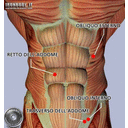

muscoli-addome-anteriori[1].jpg